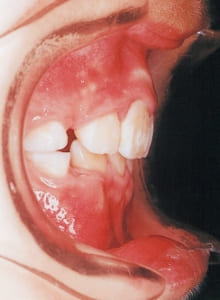

4 Initial Visit 2-11-’88

The Class II condition is pronounced, with a significant overjet of 12.5 mm(3). Although the teeth size are large, crowding is relatively mild. The maxillofacial structure has good depth and a robust bone framework(5). The mandible itself is solid , robust gonial angle, but there is significant anterior-posterior displacement relative to the maxilla(ANB 10.0°). While there is no confirmed history of thumb-sucking or similar habits, the lower lip is already pushing up against the maxillary incisors. The cause of this condition is unknown.

6 Initial Visit 2-11-’88

20 At second stage treatment initiation 9-21-’91

In the maxilla, insufficient space for canine eruption was inevitable, necessitating extraction as part of the treatment plan. The maxillary first premolars on both sides were extracted during routine observation to create space for canine eruption (14). Eventually, the canines erupted and settled into relatively favorable positions (15,19,20). In the mandibular dentition, crowding was also present, leading to extraction of the mandibular first premolars on both sides. Treatment with full bracket was then initiated (17).